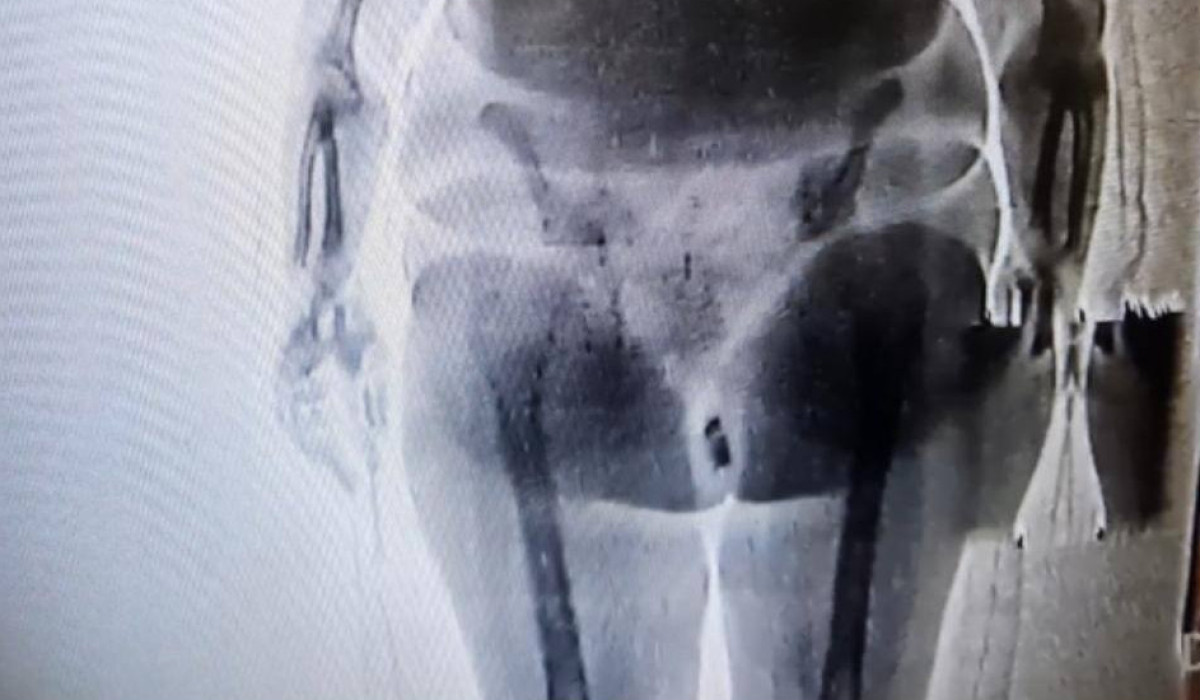

Женщина пыталась пронести в следственный изолятор телефон и SIM-карту, спрятав их в интимном месте. Она пришла на свидание со своим супругом, находящимся под следствием в СИЗО. При прохождении через рентген-устройство сотрудники увидели инородный предмет. После тщательного досмотра в женской комнате обнаружить предмет контролерами и медицинскими работниками не удалось. Как выяснилось в ходе изучения записи с камеры видеонаблюдения, женщина в комнате досмотра, до прихода медицинских работников, успела достать сверток и спрятать. В свертке были обнаружены телефон и SIM-карта.